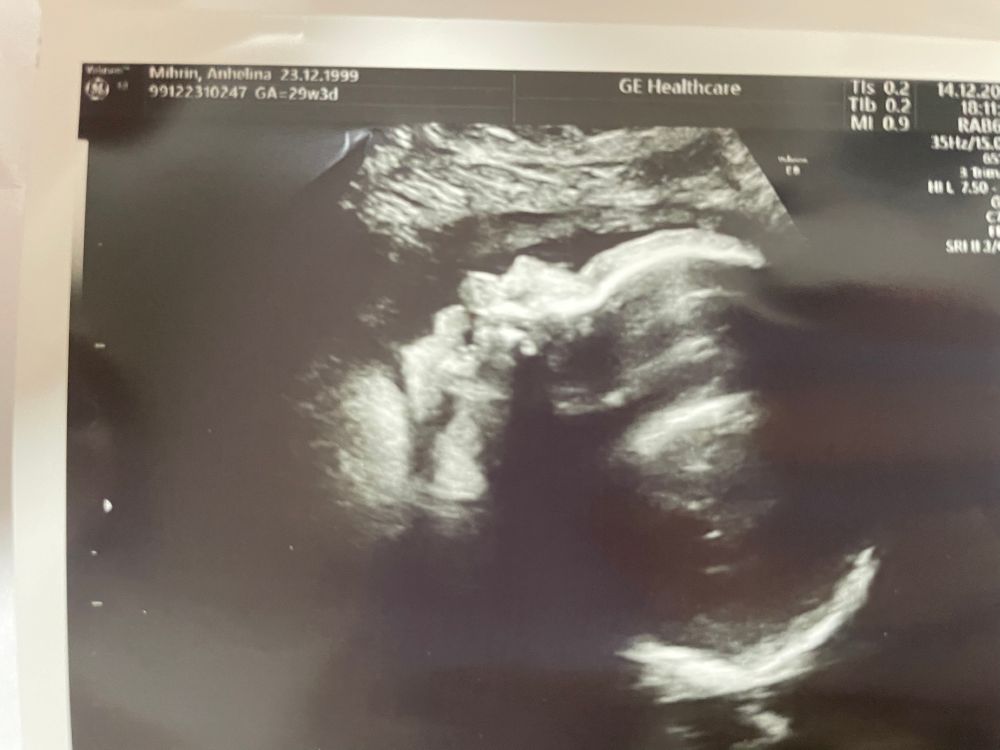

3 скрининг 💋

Наша кнопочка совсем большая стала 🥺

Вес: 1404 🌸

Все замеры в пределах нормах🙏

Личико так и не захотела показать😅 Сначала закрывалась двумя ручками, а потом показала язык и отвернулась совсем😅 Уткнулась в меня носом и не дала сделать фотографии 🥹